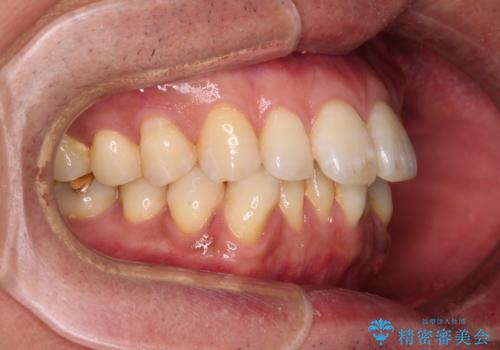

- 口元の突出感を気にして来院された患者様です。

強い咬合力と上顎前歯の傾斜により前歯が突出し、唇が閉じにくい状況であったため、上下左右の第一小臼歯4本を抜歯し、ワイヤー装置にて矯正治療を行うこととしました。